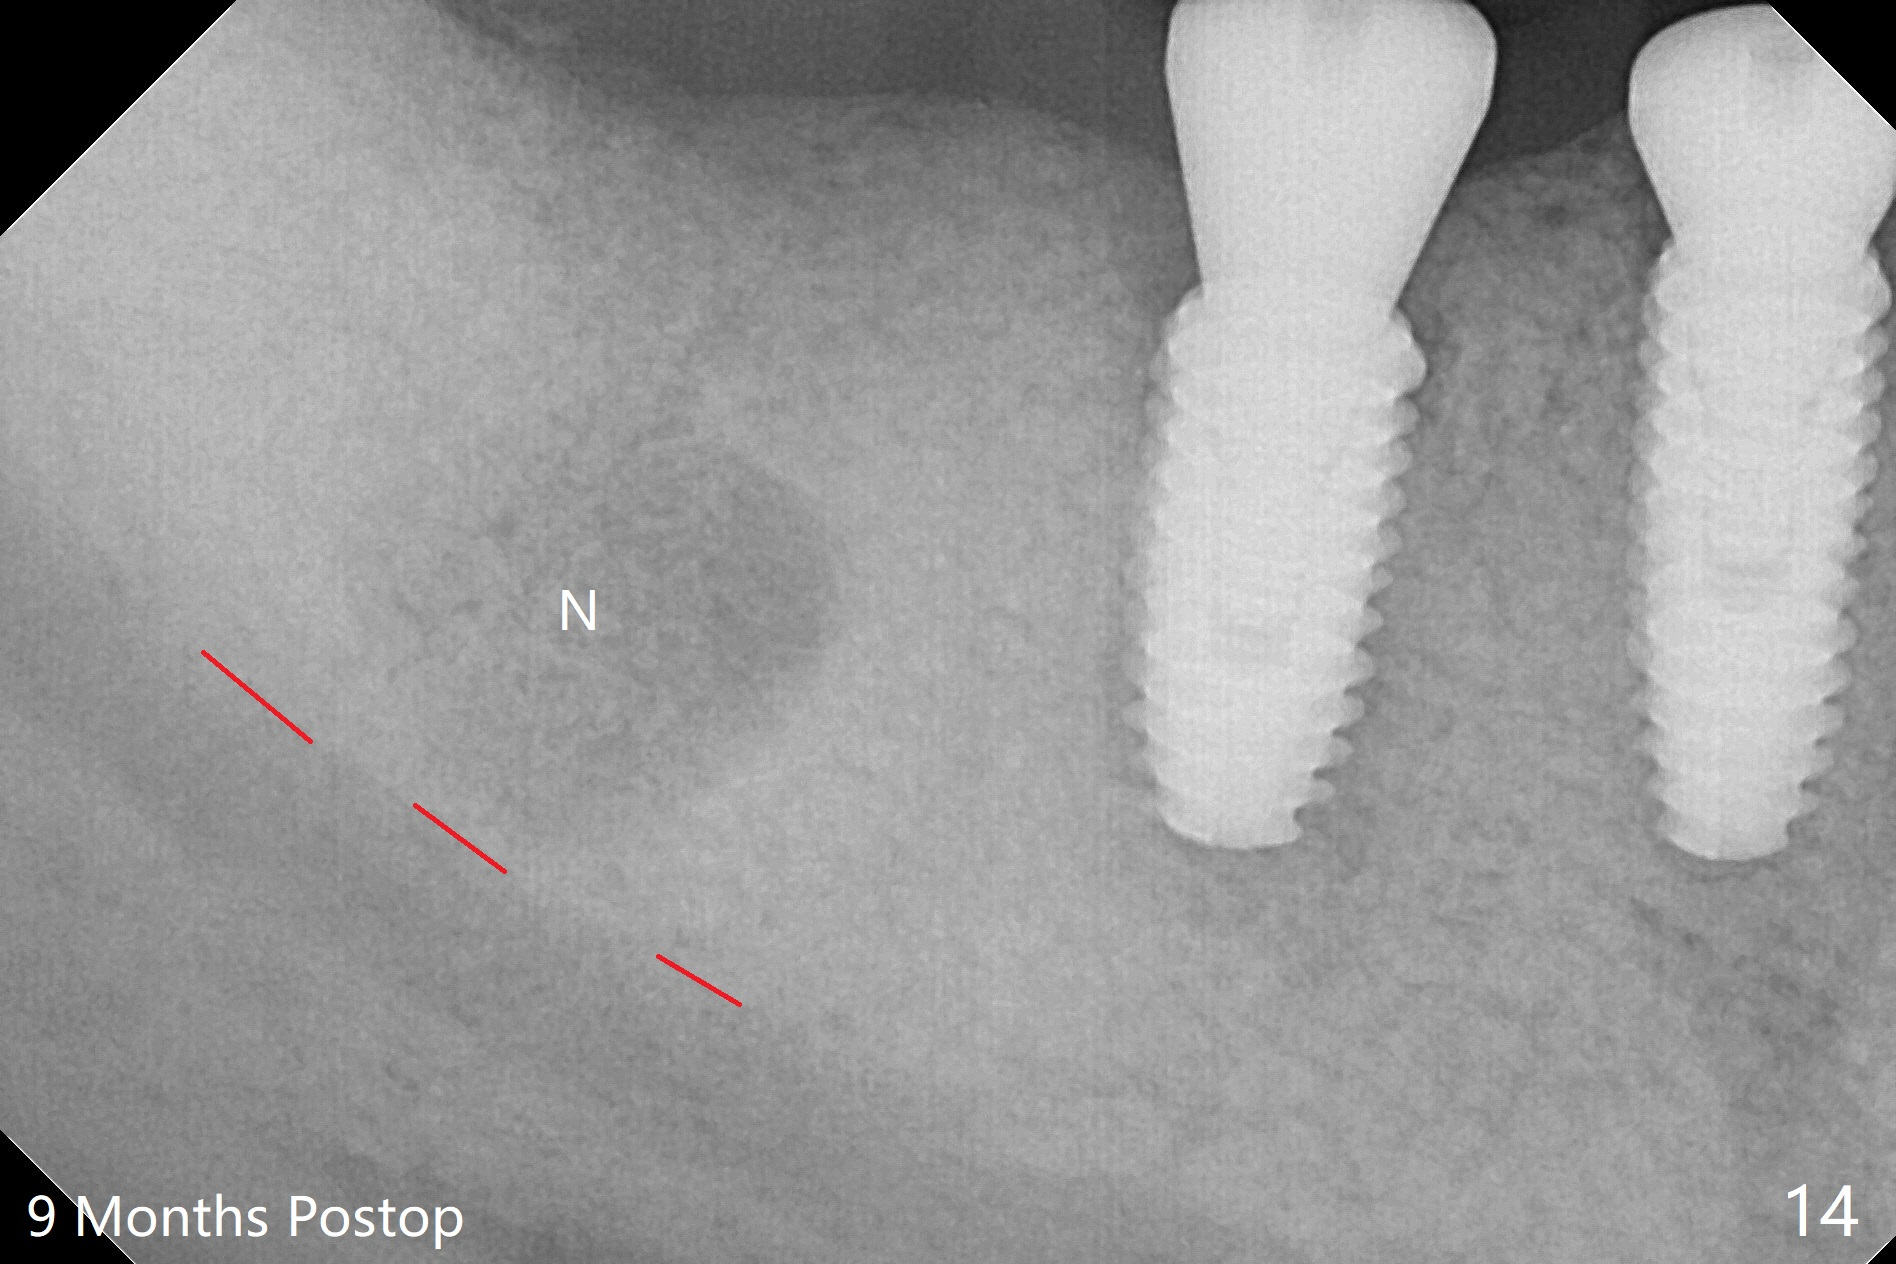

An endodontist refuses RCT retreatment at #29 because of short root. The patient is hesitant about apicoectomy. After discussion of advantages and disadvantages of the latter vs. extraction and implant, the patient chooses the extraction. The latter turns out to be smooth with socket preservation (Fig.4, 5 *). Immediately postop PA shows bone loss at #30 and minor degree around the apex of #31 implant (Fig.4 <), which is probably related with hard bone and bone necrosis due to heat. The headache disappears 1 week postop (Fig.6). The patient does not take pain medication. There is no percussion at #30 (Fig.7). The healing abutments are stable. The patient will return for #30 and 31 restoration nearly 4 months postop and 2 months post #29 extraction. Splinted provisional will be placed if the implants heal. Impression will be taken for #29 guide 4 months post socket preservation. After re-analysis of CT, it appears that a long implant (4x15 mm to gain 3.9 mm fixation in the native bone) will be placed free hand at #29 four months post socket preservation (Fig.8). The bone loss around the implants at #30 and 31 persists 3.5 month postop, while the socket heals at #29 2 months post socket preservation (Fig.9). When the healing abutments with plaque are removed, there is granulation tissue around the gingival cuffs with tenderness. The abutments with heavy plaque (similar to that in Fig.7) are reloaded after cleaning with OHI. The patient returns for CT and impression for #29 guide 3.5 months post socket preservation and 5 months post implant placement. While bone necrosis remains severe at #30, the socket at #29 seems to have healed (Fig.10). Oral hygiene improves with healthy gingiva, but there is tenderness when a cementation abutment is placed. Implant design before and after extraction at #29 (Fig.11,12). Gingiva becomes inflamed at #31 when a splinted provisional is being worn to intrude the opposing supraerupted teeth; bone resorption remains severe in the previous distal socket and the mesial necrotic area (Fig.13 S, N). Pain persists after placement of a healing screw. In spite of severe bone loss, especially distal, the buccal plate is present. When the implant at #31 is removed, there is a large defect with granulation tissue apicobuccal to the buccal plate, corresponding to the presumptive mesial necrotic area (Fig.13,14 N). Vanilla graft mixed with PRF ("sticky bone" too rigid) is placed in the defect, followed by a piece of PRF membrane and 6-month one. The pain appears not to reduce and nearly 1 month later transfers to the buccal of #30.